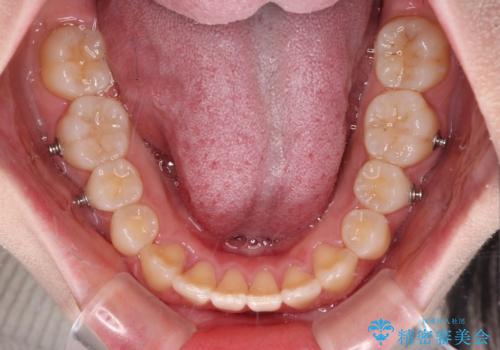

ディープバイトをインビザライン矯正で改善

- インビザライン

- 1年7ヶ月

インビザラインを用いて、前歯の叢生を解消するとともに、ディープバイトを改善していくこととしました。

上顎に乳歯が左右1本ずつ残っていたため、若干咬み合わせに不具合が残りましたが、強い咬合力の原因であったディープバイトをしっかりと改善することができました。